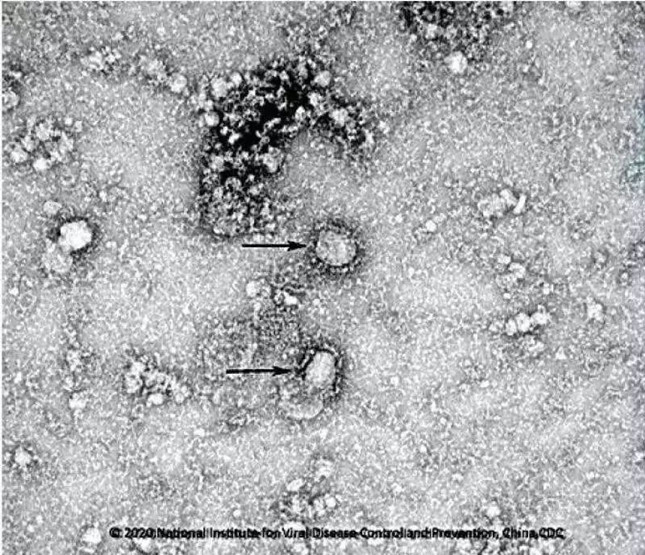

1. 什么是武汉新型冠状病毒?

从武汉市不明原因肺炎患者下呼吸道分离出的一种新型冠状病毒,已被世界卫生组织命名2019-nCoV。